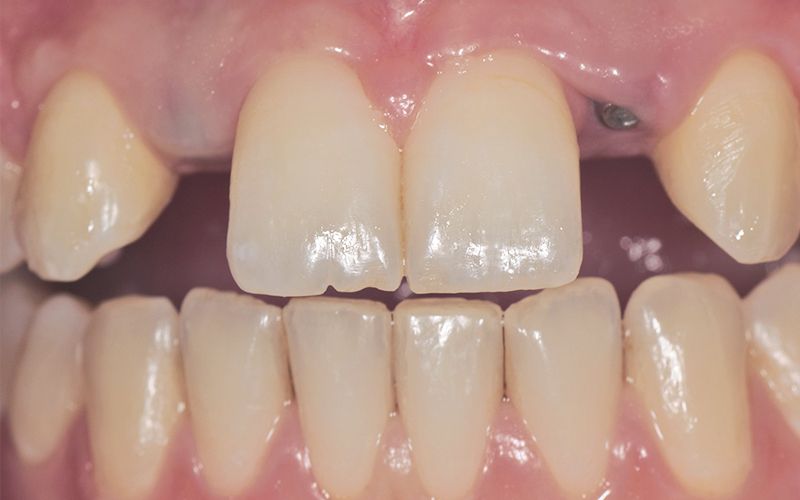

Paciente mujer de 16 años acude a la clínica por motivo de agenesia de los incisivos laterales superiores 12 y 22. La paciente no presentaba antecedentes médicos de interés y a la exploración clínica y radiográfica se observó que gozaba de una excelente salud oral. Derivamos a la ortodoncista que, tras un estudio pertinente, inició un tratamiento con brackets para tratar de lograr el espacio máximo entre los centrales y caninos con el propósito de colocar dos implantes a futuro.

Al cabo de todo este tiempo se realizó un CBCT maxilar para iniciar la planificación de la cirugía de colocación de dos implantes en posición de 12 y 22. Durante el análisis de las imágenes radiográficas, tal y como indican las mediciones que se realizaron, se observó una limitación de espacio en sentido mesio-distal entre 11 – 13 y 21 – 23, que iba a impedir la colocación de dos implantes estándar de 3.3 mm de diámetro.